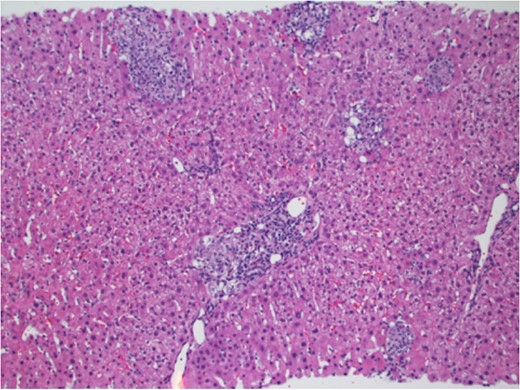

In March 2017, the patient presented with 2 weeks of generalized body aches, fevers, mild congestion and dysuria. His transaminases worsened—AST 360 U/L, ALT 387 U/L. Blood, urine and sputum cultures grew no organisms and the patient had a normal chest radiograph and abdominal ultrasound. CT sinus, obtained to rule out sinusitis, remarked on few mucous retention cysts of the maxillary sinuses, but was otherwise negative for any other pathology. However, further interrogation found that the patient had significant opportunistic infection exposure risk; the patient was a butcher at a local grocery store, and owned a new rabbit, several parakeets and four dogs. A repeat liver biopsy was performed, and this time, was found to have predominantly lobular, and occasionally portal, epithelioid granulomas (Fig. 1) with intracellular yeast-like elements (Fig. 2). These were described as narrow-based budding yeasts favoring histoplasma (Fig. 3). No portal based features of acute rejection were noted and bile ducts were preserved in the majority of portal tracts. Urine histoplasma antigen testing corroborated the histology finding—the patient had progressive disseminated histoplasmosis manifested as granulomatous hepatitis. He completed an 11-day course of liposomal amphotericin B and will continue itraconazole therapy for a year. His immunosuppression regimen was significantly decreased and mycophenolate was stopped. The most recent liver biopsy in May 2017 revealed a persistent—though significantly decreased—lobular inflammation, microgranulomas and budding yeast elements. His transaminases remain elevated at AST 265 U/L and ALT 259 U/L. He will continue close follow up to ensure further improvement on current therapy and resolution of Histoplasmosis.

Grocott methanamine silver stain showing yeast-like fungi with narrow-based budding, consistent with histoplasma ×400.